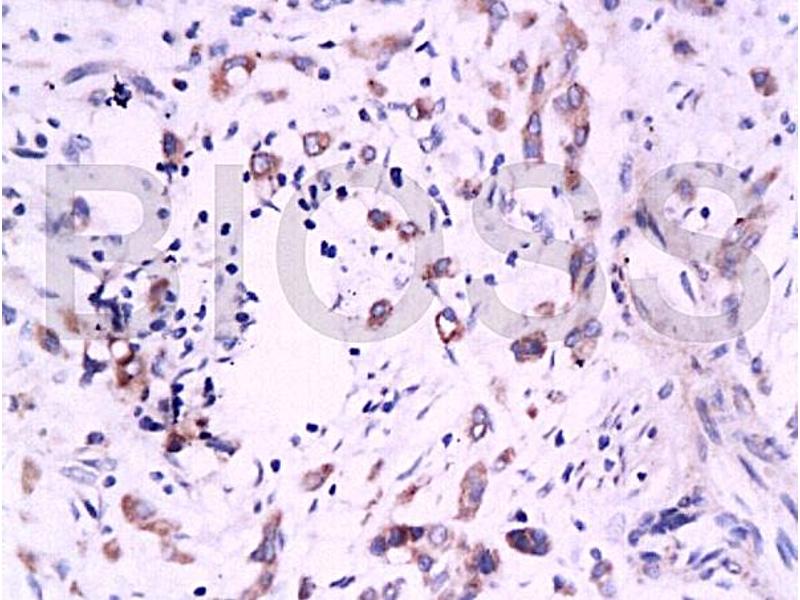

Durch die Bindung an verschiedene Regionen eines Antigens zeigen polyklonale Antikörper eine zuverlässige Performance in Anwendungen, bei denen Epitope teilweise denaturiert oder maskiert sein können, wie z. B. Western Blot oder Immunhistochemie (IHC). Sie werden häufig in ELISA, WB, IHC, IF und Immunpräzipitation eingesetzt, wenn eine starke und konsistente Signalgebung erforderlich ist.